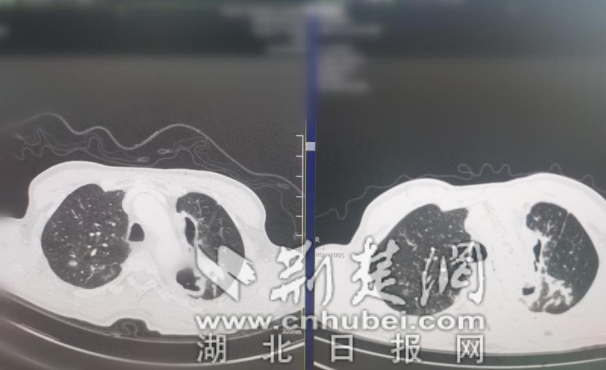

女子腹痛竟是胃“移位”入胸腔 医生巧补“破洞”让胃安全归位

她未曾想到,自己胸腔与腹腔之间的屏障——“膈肌”竟出现了两处破洞,导致三分之二的胃体“闯入”胸腔。[查看全文]